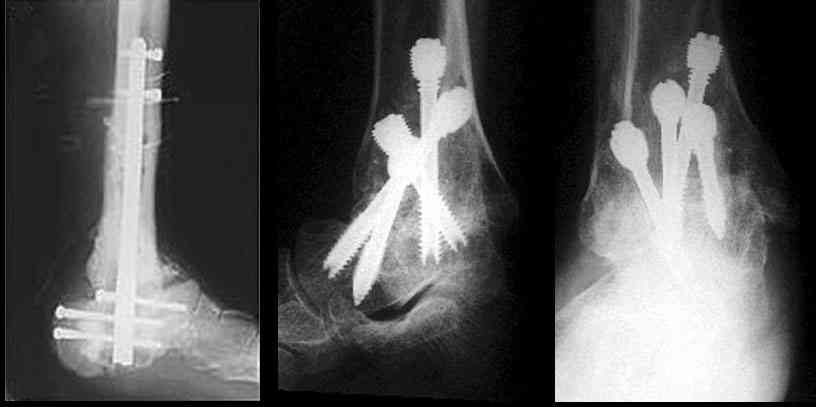

Существуют специальные системы для артродеза голеностопного сустава. См. приложение